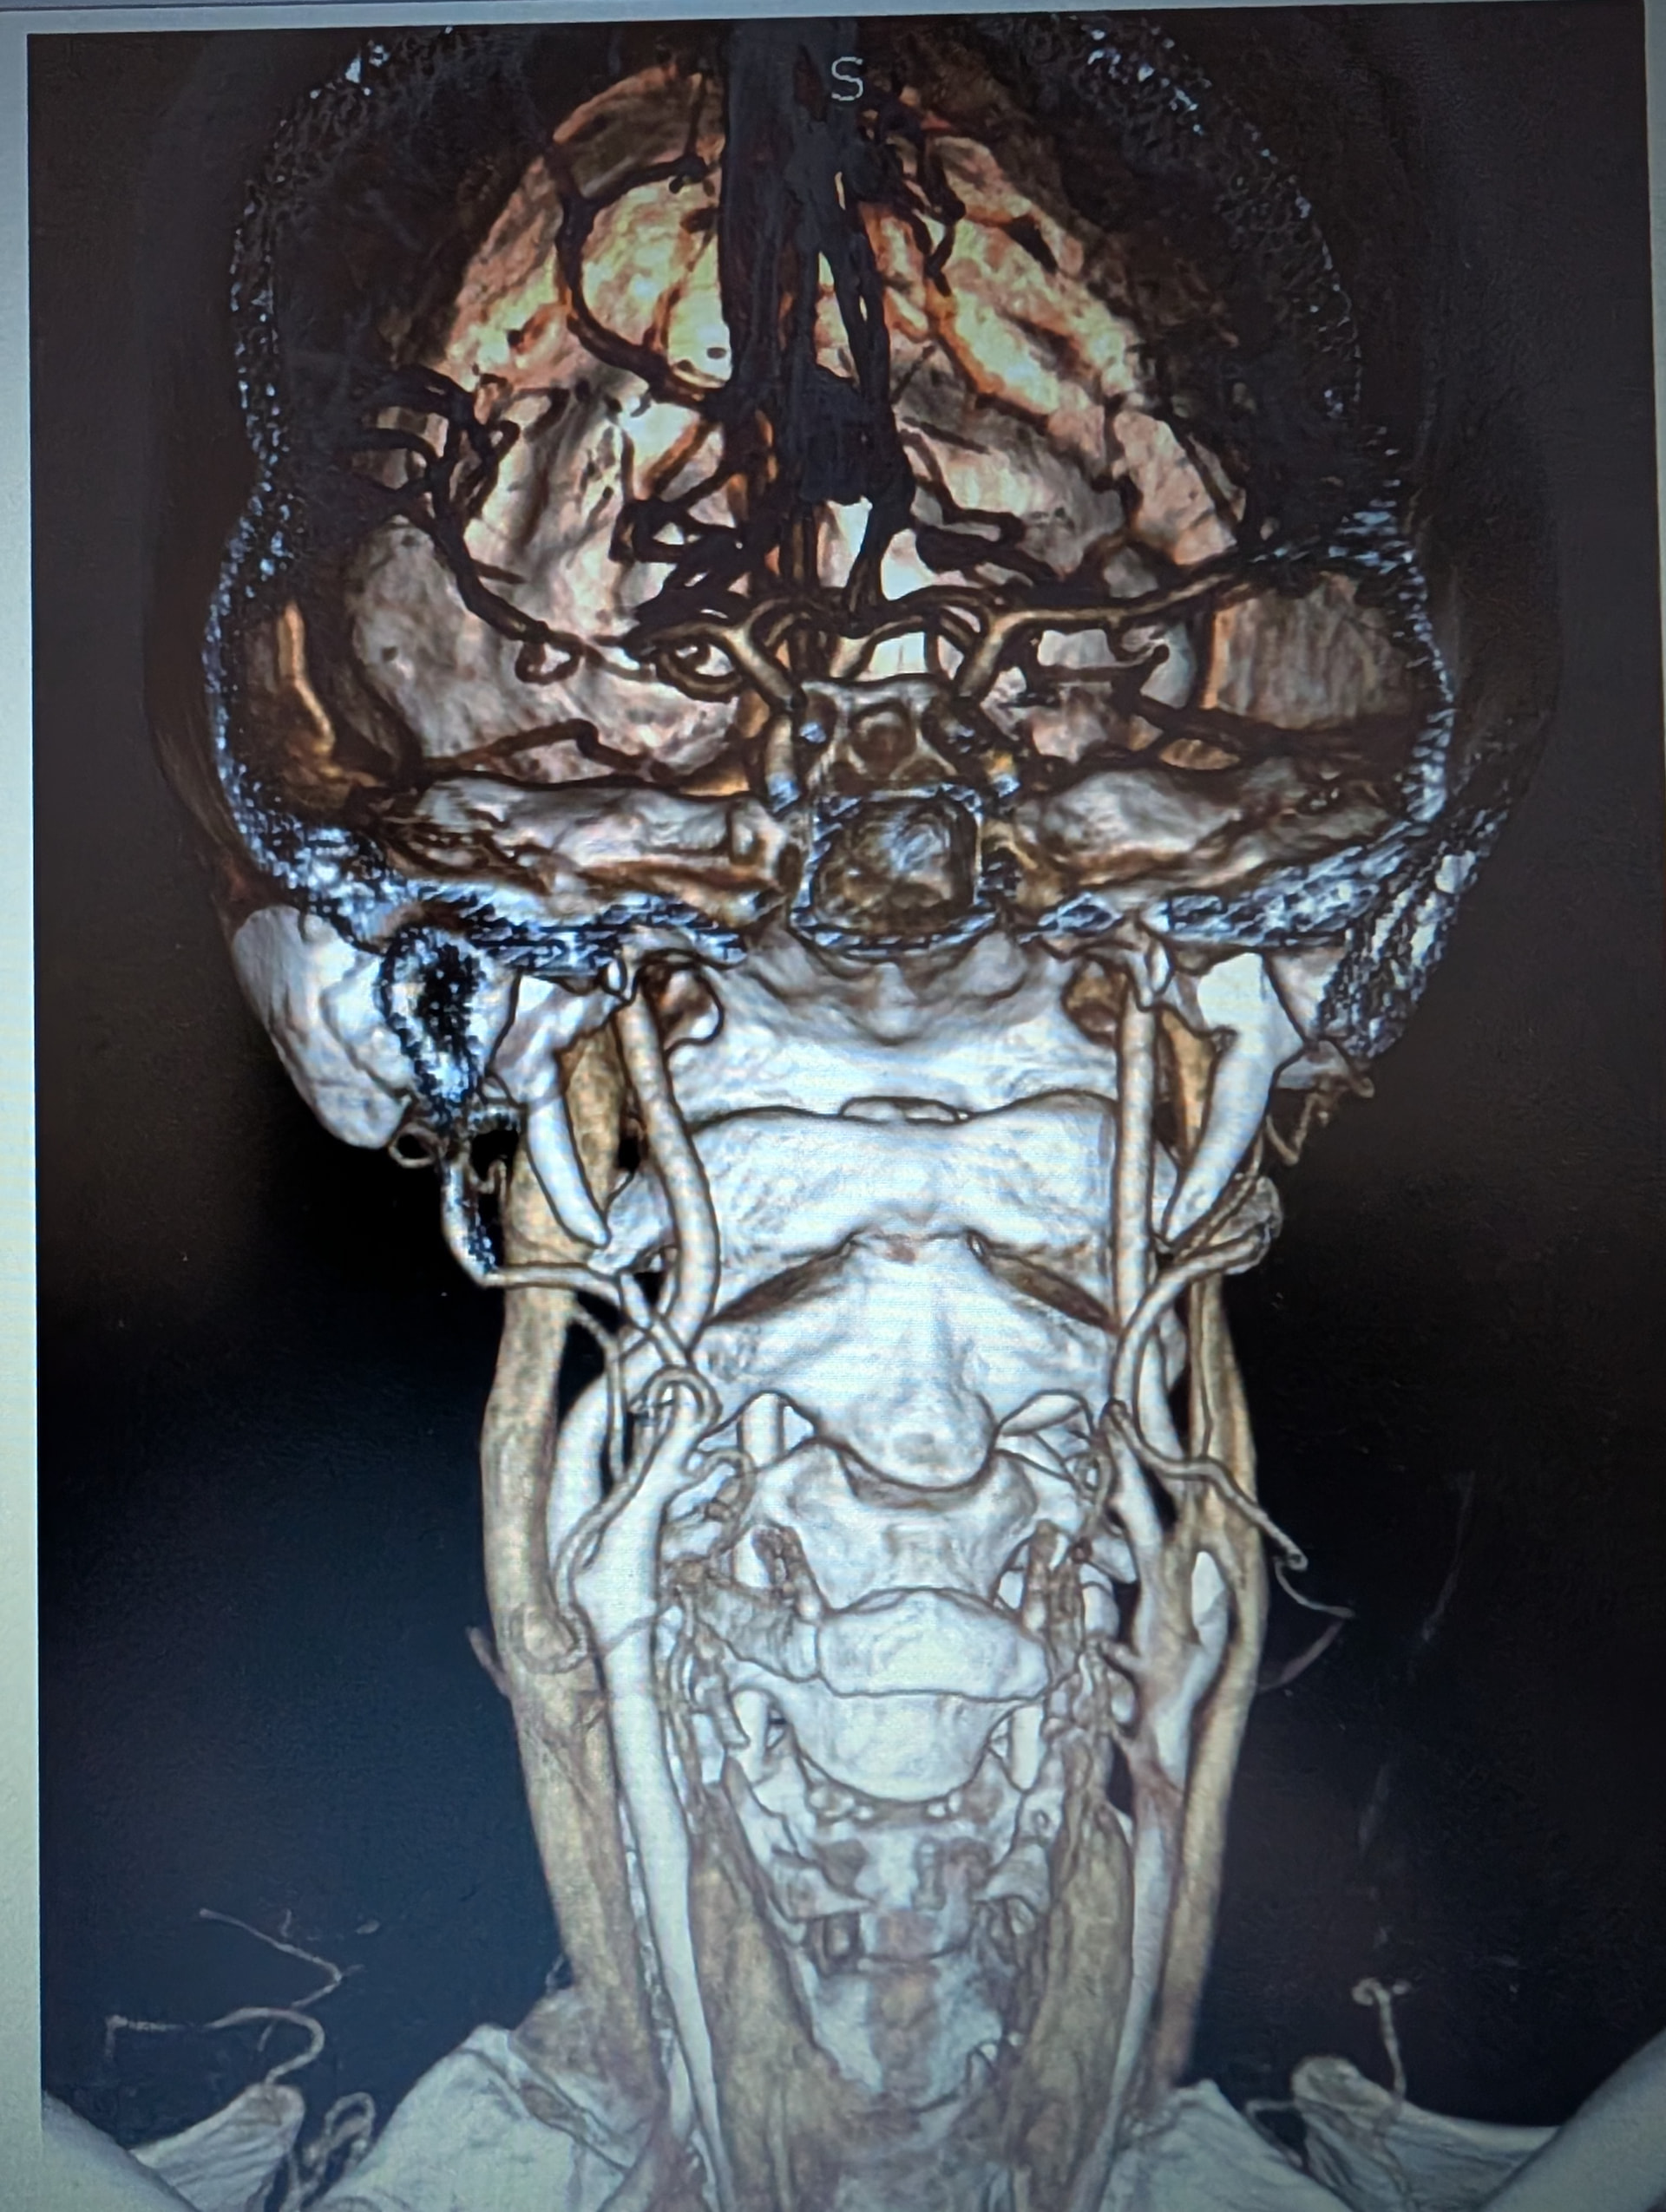

I have edited my post one more time, it must be my anxiety. I have added a picture of my scan with contrast. My elongated styloid processes are trapping my jugular vein. My carotid artery is off track… :scream:

@Hamela - Your styloids aren’t terribly long, but they are exceedingly thick, especially the left one which is a bit more angled than the right one. The right one is more curved. The thickness & angles of growth can significantly play into the symptoms & compression the styloids are causing.

I don’t know how significant it is that your right internal carotid artery is out of place even though Dr. Middleton made note of it, unless you’re also having symptoms related to your carotid artery which would be facial numbness, eye pain, neck pain, temporary visual loss or partial visual loss in one eye, dizziness, & headaches (these may differ somewhat from those caused by IJV compression). TIAs (mini strokes) are often also a symptom pointing to compression or irritation of the carotid artery(ies). It is possible your body has simply adapted to its new location w/o any problem.